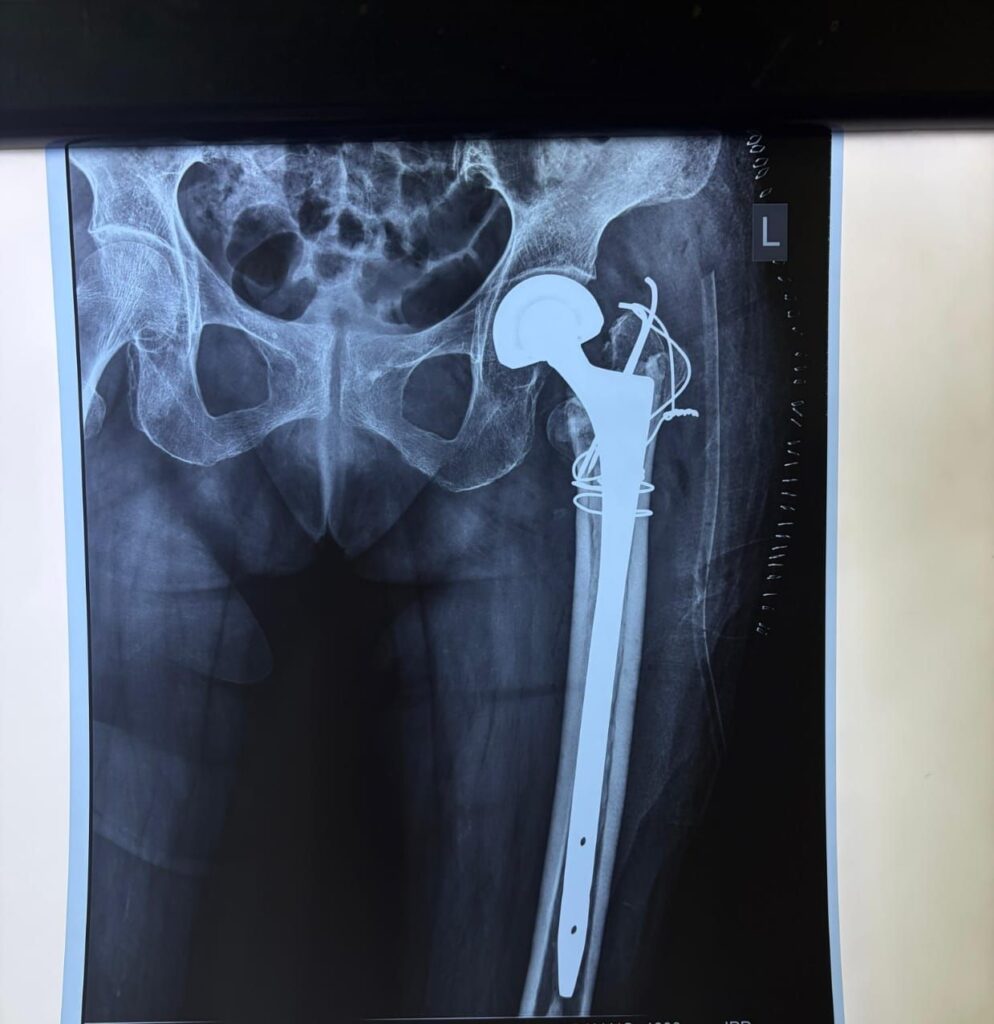

मरीज की हालत को देखते हुए विभागाध्यक्ष डॉ. बेन के मार्गदर्शन में चिकित्सकों की टीम ने लंबे स्टेम वाले मॉड्यूलर बाइपोलर कृत्रिम कूल्हा प्रत्यारोपण, टीबीडब्ल्यू तकनीक तथा एन्क्लेज वायरिंग की मदद से जटिल ऑपरेशन को सफलतापूर्वक अंजाम दिया।

सर्जरी के बाद बुजुर्ग महिला में तेजी से सुधार हुआ और ऑपरेशन के अगले ही दिन वह खड़े होकर चलने-फिरने लगी, जिसे चिकित्सा क्षेत्र में एक बड़ी उपलब्धि माना जा रहा है।